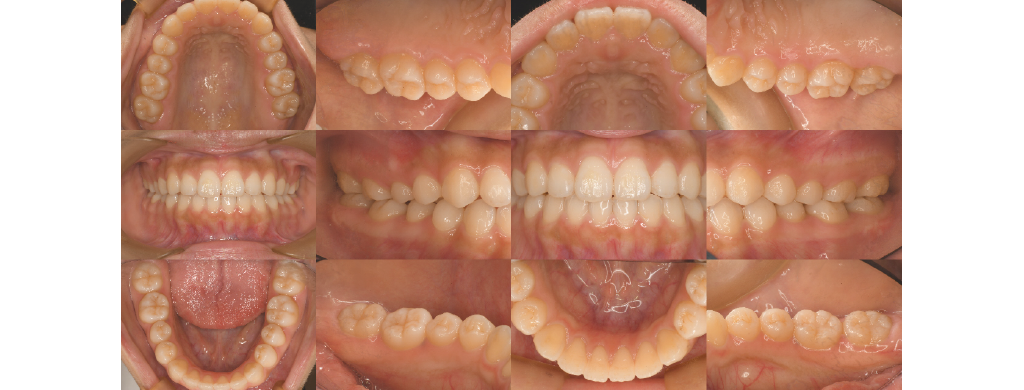

- 口腔内規格写真(12枚法)

鏡では見えにくい歯の裏側まで鮮明に撮影。

治療前後の比較にも活用します。